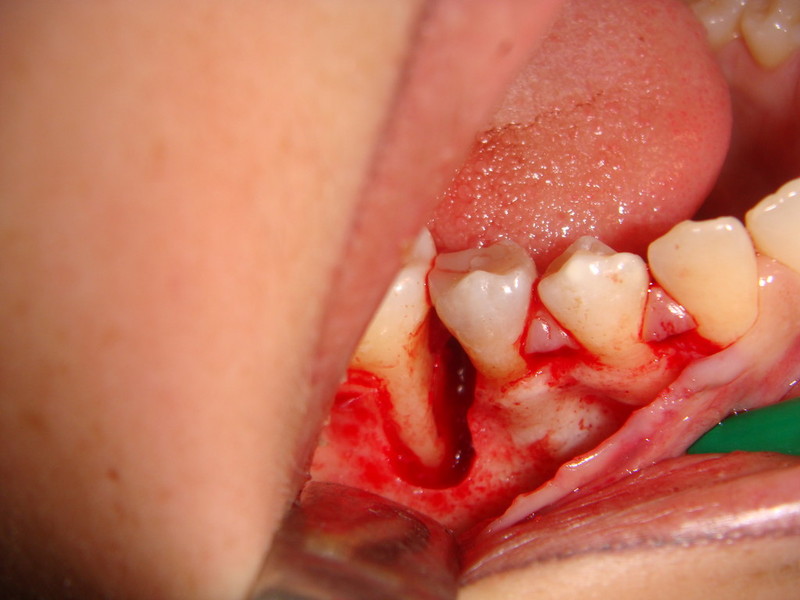

Rigenerazione Gravi difetti parodontali

Rigenerazione difetto parodontale di un canino inferiore con materiale eterologo